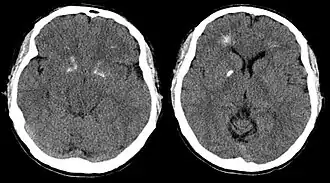

Компьютерная томограмма головного мозга пациента с синдромом Ди Георга демонстрирует кальцификацию базальных ганглиев и перивентрикулярное обызвествление. (По материалам Tonelli et al., 2007).